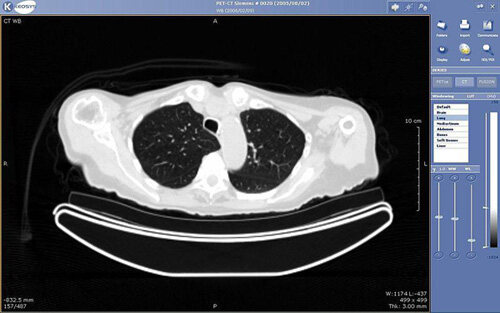

PACS主要包括四个组成部分:影像学检查如X光、平片(PF, Plain Film)、电子计算机断层扫描(CT, Computed Tomography)和核磁共振(MRI, Magnetic Resonance Imaging)。与新兴的网络技术相结合,PACS已经具备能够及时有效访问影像、相关资料和数据的能力。它打破了传统的以胶片为基础的影像检索、分配与呈现方式等物理和时间的限制,是集影像采集传输与存储管理、影像诊断查询与报告管理、综合信息管理等于一体的综合应用系统。

一个典型的PACS系统由许多设备与程序组成。首先是PACS的形态,如CT、超声波、核医学机器和核磁共振等,随后它们被发送到QA(Quality Assurance)工作站。QA工作站是一个确保病人的资料以及重要特征是否正确的检查站。若信息确认无误,那么影像就会经过归档系统进行储存。核心储存设备能够存储病人的医学影像、诊断报告、检查数据和其他与影像有关的信息。

PACS工作流的第二步是阅读工作站,它能够协助放射科医生研究病人的影像资料并给出病人的最终诊断结果。越来越多的PACS系统利用网络接口作为其通信手段,如VPN或SSL等。PACS影像备份是一个极易被忽略但十分重要的部分。为防止病人影像资料丢失,HIPPA要求其影像有备份的副本,而且这些副本应自动被发送至异地且独立的计算机进行妥善储存。